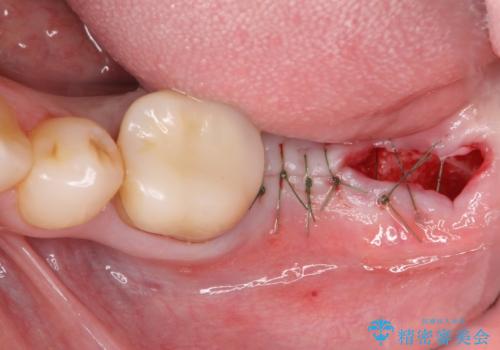

不適合ブリッジの除去 インプラントによる咬合再構成

清掃性の悪いブリッジ・親知らずを除去し再根管治療・インプラントを含めた咬合再構成の計画を立てます。

- 50万円(ストローマンインプラント・骨造成・チタンカスタムアバットメント・メタルボンド×2)費用は治療当時の料金となります

- 外科手術のため、術後に痛みや腫れ、違和感を伴います